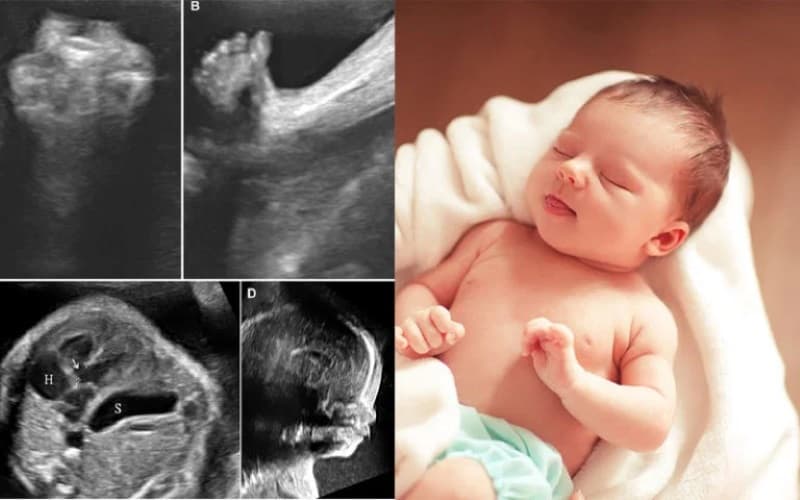

1.2. Kích thước thai nhi 33 tuần và các chỉ số quan trọng

Bên cạnh việc theo dõi xương đùi, thai phụ cũng cần nắm bắt một vài số đo hình thể khác. Những dữ liệu này giúp phác họa bức tranh toàn cảnh về kích thước thai nhi 33 tuần:

- Trọng lượng của em bé ước tính đạt từ 1,807kg đến 2,419kg.

- Chiều dài cơ thể tính từ đỉnh đầu đến gót chân xấp xỉ khoảng 43,7cm.

- Đường kính lưỡng đỉnh (BPD) phát triển ổn định trong khoảng 75mm đến 90mm.

- Chu vi vòng đầu (HC) ở mức 279mm đến 326mm.

- – Chu vi vòng bụng (AC) dao động từ 257mm đến 319mm.

Ở tuần thai này, hệ thần kinh và bộ não của trẻ đã phát triển gần như hoàn thiện. Bé có khả năng lắng nghe, cảm nhận và đôi mắt đã biết phản ứng với ánh sáng. Đồng thời, lớp mỡ dưới da tiếp tục tích tụ mạnh mẽ giúp bé giữ ấm sau khi chào đời.